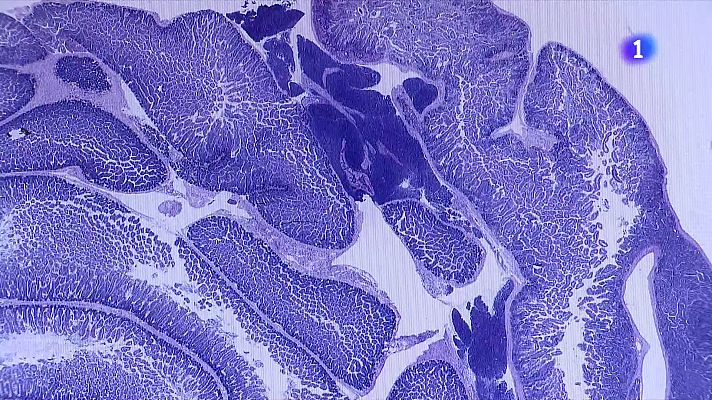

L’Hospital Vall d’Hebron ha posat en marxa una unitat pionera per estudiar les alteracions en la biologia dels telòmers en adults. Aquestes estructures cromosòmiques poden provocar malalties vinculades a l’envelliment quan presenten mutacions. La unitat ja ha diagnosticat una trentena de casos i estudia l’entorn genètic familiar per millorar la qualitat de vida dels pacients.